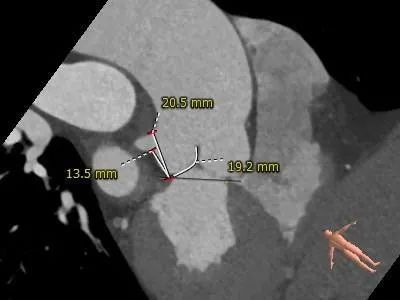

主动脉根部测量:

冠脉测量:

冠脉开口高度可,切线角度测量,左窦瓣叶长于左冠开口下缘